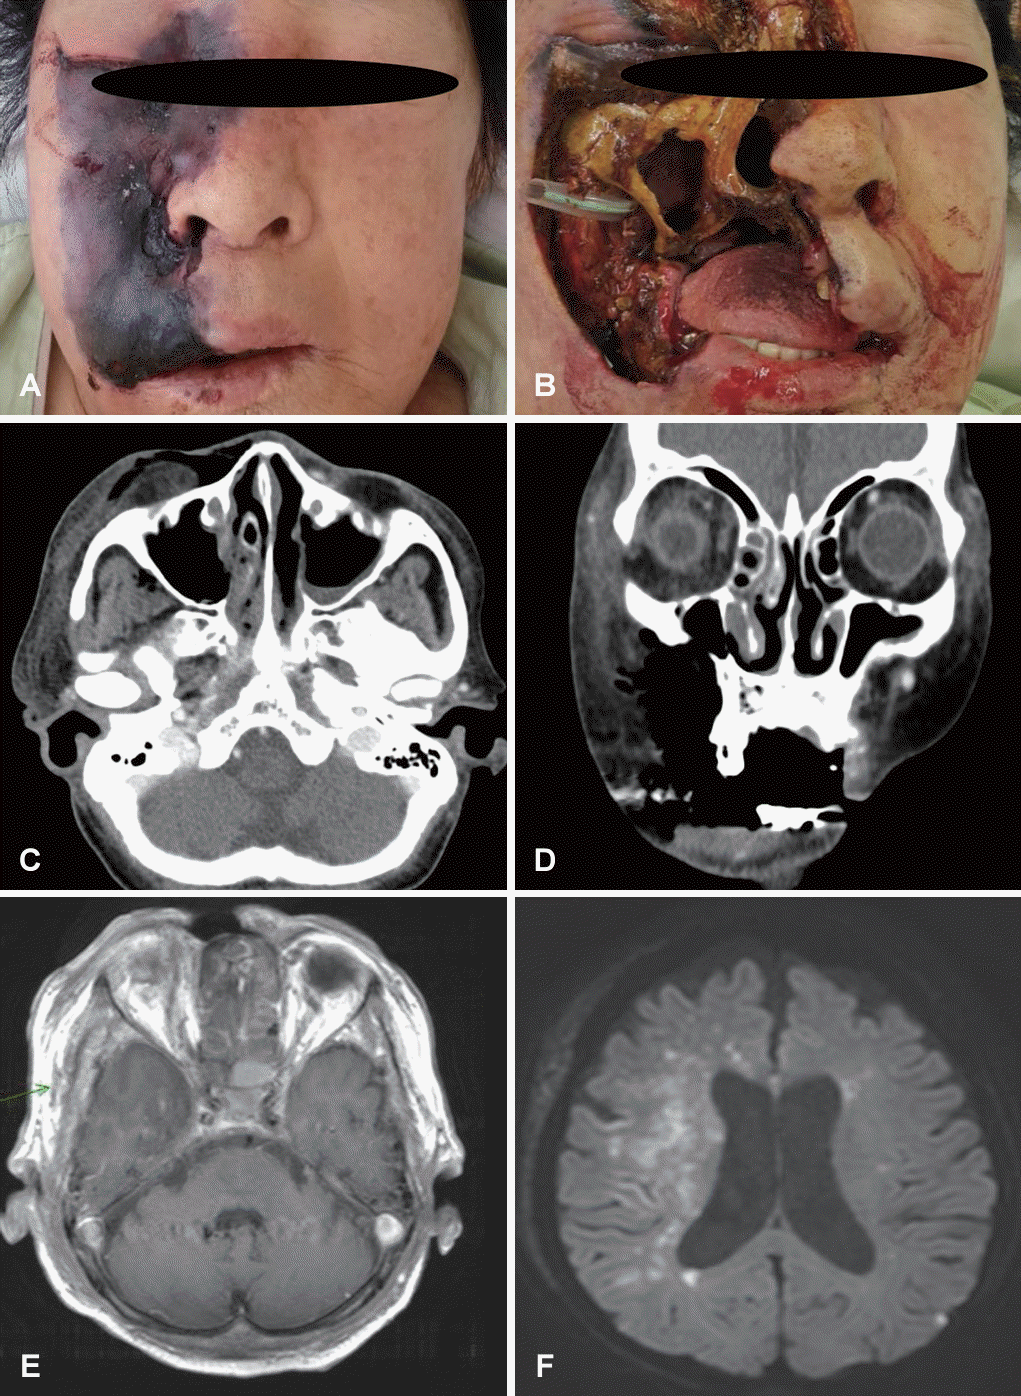

A seventy-five-year-old female with diabetes and liver cirrhosis was referred to our clinic with three days of progressive right facial swelling and pain. She had a history of treatment for Bell’s palsy one week before, with three times of acupuncture. The initial physical examination showed small black eschars on the right cheek, with black necrotic skin lesions from the lower lip to the eyebrow (Fig. 1A). As the extent of the lesion was rapidly increasing within a few hours, she was emergently admitted for rapid diagnostic work up and treatment.

A contrast-enhanced CT scan of the head and neck was performed, and it showed a right anterior maxillary wall defect and hemifacial cellulitis with air formation without definitive abscess formation (Fig. 1C and D). Considering disease progression, empirical intravenous antibiotics were initiated with piperacillin/tazobactam, clindamycin, and vancomycin, and surgical debridement was carried out at the same time. Extensive debridement was performed until fresh tissue was seen, and most of the nasal mucosa, partial nasal bone, and partial anterior maxilla were resected and drilled out as they were found to be necrotic (Fig. 1B). The surgical defect in her facial lesion was initially planned to be reconstructed with a secondary surgery, such as an anterolateral free flap, after complete recovery from the infection, depending on the extent of the defect.

The pathologic diagnosis was confirmed as invasive mucormycosis (Fig. 2), and intravenous amphotericin B liposome (ambisome) was added to the patient’s treatment regimen. Despite management, her mental status changed to confusion with left-eye pupil dilation on the third day of admission. Brain magnetic resonance imaging showed multifocal acute ischemic lesions near the right middle cranial artery and the left corona radiata. In addition, both cavernous sinuses and internal carotid arteries appeared to be involved with invasive mucormycosis (Fig. 1E and F). Given the patient’s anticipated fatal prognosis due to disease progression and brain infarction, her family chose not to pursue further surgical interventions or diagnostic procedures. The patient developed septic shock from the progressive infection, exhibited unstable vital signs and a loss of spontaneous respiration, and passed away on the sixth day of hospitalization.

Fig. 1.

Facial photo and radiologic images of the patient. A: The initial physical examination shows blackish eschars on the right side of the face. B: Extensive debridement was performed, including the facial skin, maxillary bone, and nasal mucosa. C and D: Preoperative axial (C) and coronal (D) contrast-enhanced CT scans showed cellulitis with air formation without any definitive abscess. E: T1-weighted contrast-enhanced MRI revealed involvement of the cavernous sinus and internal carotid artery by infection. F: Diffusion-weighted imaging showed multifocal acute ischemic lesions on the right middle cerebral artery territory and the left corona radiata.